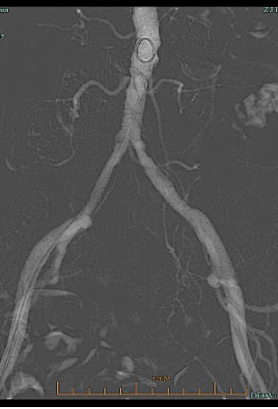

术前CTA:腹主及双侧髂动脉多处钙化病变伴管腔狭窄。

经腹主动脉造影如术中所见双侧髂动脉中-重度狭窄。

★ 术后CTA

显示钙化病变重塑,双侧髂动脉管腔较前明显改善